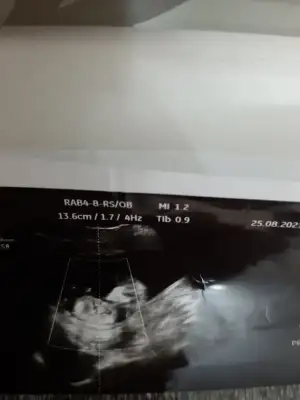

dr soylemeden siz gorun genital nub teorisi ( bebegin cinsiyeti)

MerhabaNet değil o nedenle yazmadım başka USG varsa paylaşın 10-11-12-13

Evet kız Gibi görünüyor

Erkek sanki emin olamadım başka USG varsa paylaşın

Biraz aşağısıIkra meyra nub işaretlemişim yer mı oluyor canım

Evet bende emin olamadım12 haftalık doktor kız gibi dedi ama yanılma çok oluyor dedi 1 ay sonra netleştirirz dedi bazen pipilerini göremiyoruz dedi çok ufak olduğu için yanılabilriz dedi

Bizde bugün kontrolden çıktık 12+3 haftalığız ,doktor cinsiyet için emin olamadı resimlerden siz yorum yapabilirmisiniz

Bu hafta da nub yanıltır cnm en iyi 11 12 13 haftalar olmalıIkra meyra gözükmüyor o zaman değil mi bu ultrasonda

Tamam çok teşekkürlerBu hafta da nub yanıltır cnm en iyi 11 12 13 haftalar olmalı